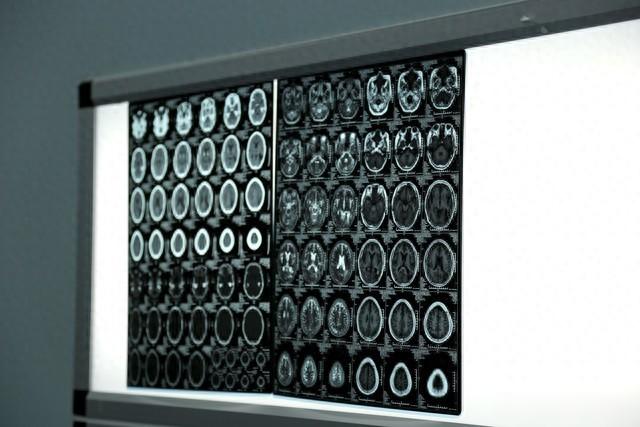

刘女士,60岁,近两个月来被持续性头晕与颅内持续的“嗡嗡”声严重干扰生活。曾多方求医,症状始终未能缓解。辗转来到上海交通大学医学院附属第九人民医院神经外科,经反复检查明确病因——颅内静脉血流异常。

诊疗团队为刘女士成功实施了精准的神经介入手术。当刘女士从手术中醒来,第一个映入脑海的感受,不是疼痛,而是一种令人难以置信的……宁静。“消失了,那个声音真的完全消失了!”困扰她两月有余的轰鸣与眩晕,像退潮般悄然离去,留下了久违的宁静。